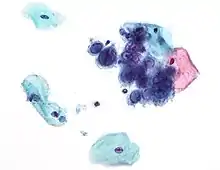

Micrograph of a Pap test showing a low-grade intraepithelial lesion (LSIL) and benign endocervical mucosa. Pap stain. Micrograph of a Pap test showing trichomoniasis. Trichomonas organism seen in the upper right. Pap stain.

Micrograph of a Pap test showing trichomoniasis. Trichomonas organism seen in the upper right. Pap stain.